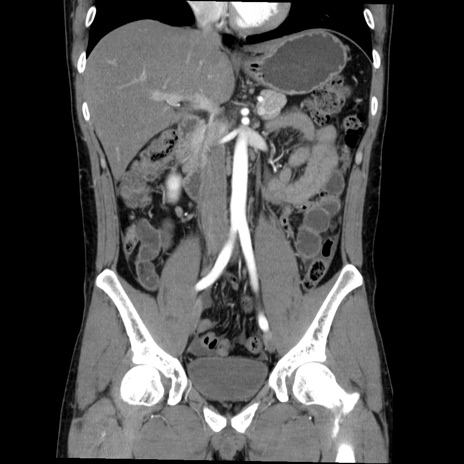

症例36(冠状断像)

【症例】20歳代 男性

【主訴】心窩部痛

【現病歴】今朝より上腹部痛あり。一旦軽快していたが再度出現したため救急要請。昨日夕に白身の魚を含む刺身を食べた。

【身体所見】BP 136/89mmHg、HR 74/min、BT 37.0℃、腹部:膨満、軟、心窩部に圧痛あり。反跳痛なし、筋性防御なし、腸雑音やや亢進あり。

【データ】WBC 17700、CRP 0.48